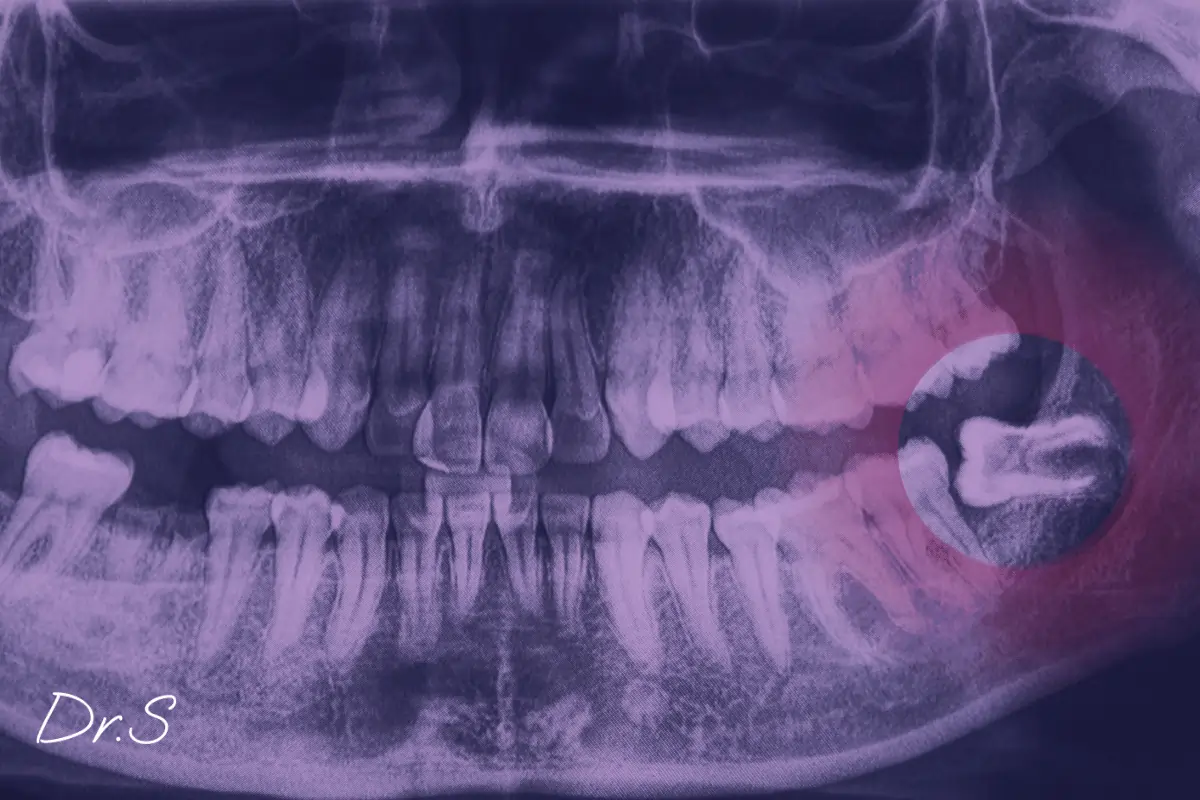

Certains actes chirurgicaux ne peuvent être différés. C’est le cas de l’extraction d’une dent de sagesse infectée, du drainage d’un abcès, ou de la réduction d’une petite fracture. Ces interventions peuvent parfois être réalisées dans des conditions ambulatoires, en cabinet ou au bloc avec anesthésie adaptée.

Les traumatismes du visage sont fréquents après un accident de sport, une chute ou un choc. Ils peuvent provoquer des plaies, des dents cassées, ou des suspicions de fracture de la mâchoire. Le plus souvent, une évaluation clinique et radiologique permet d’établir le diagnostic.

J’utilise l’imagerie 3D lorsque cela est nécessaire, notamment pour visualiser des lignes de fracture invisibles à l’œil nu. Si une réduction de fracture est indiquée, celle-ci peut être réalisée en urgence, parfois sous anesthésie générale en milieu hospitalier, en lien avec les chirurgiens maxillo-faciaux.